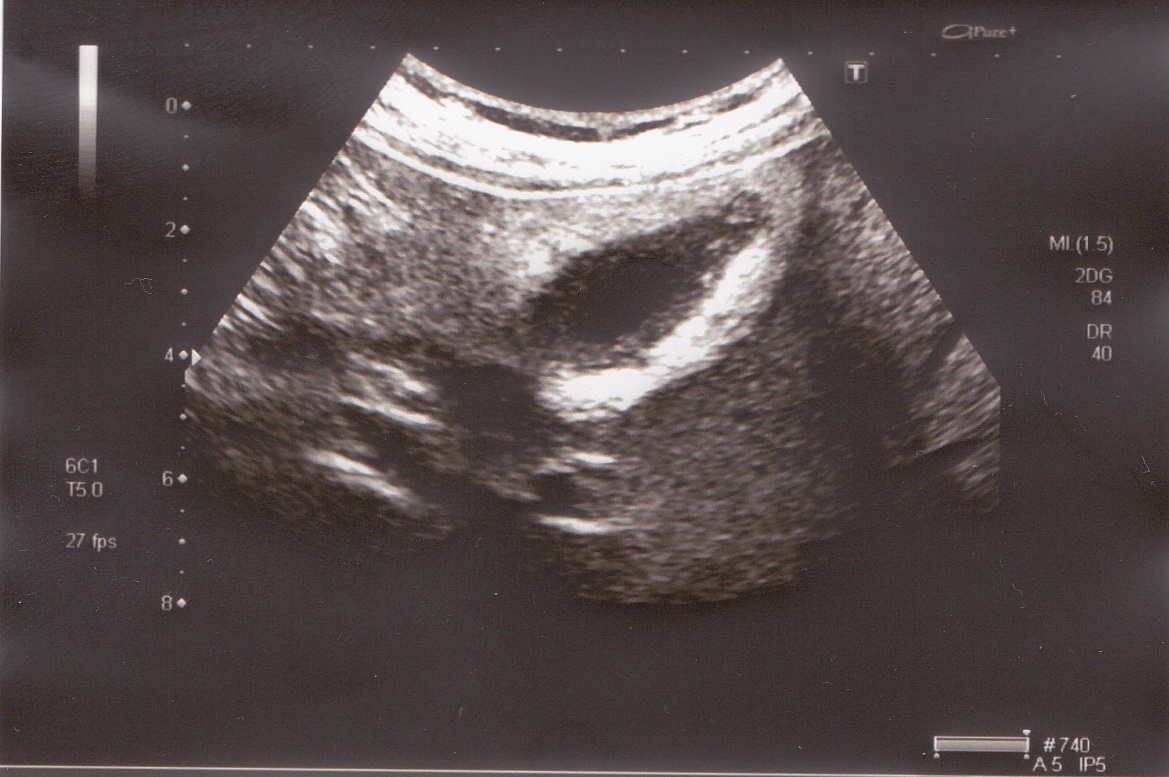

вот непонятно,что это и к чему относится. слизистая такая может быть?

желчный в поперечнике.

при ЦДК и ЭД кровоток не регистрируется в области стенки. 2й "слой" охватывает пузырь внутри циркулярно. содержимое анэхогенное, при перемене положения тела- на боку,на животе,сидя,стоя,лежа на спине- ничего никуда не перемещается.